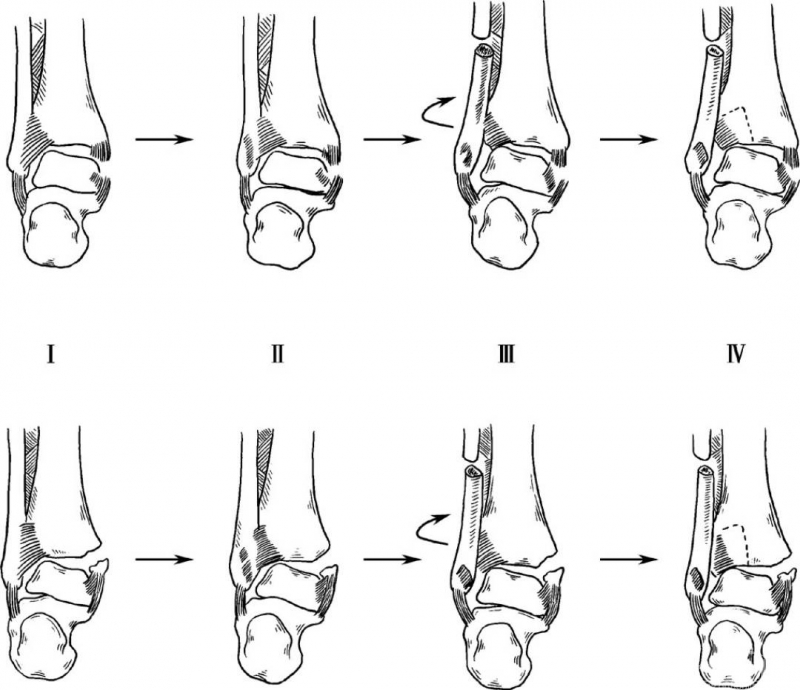

2. 旋后—外旋型

当患足处在旋后位时,此时如受外力迫使躯体内旋,患足相对外旋下胫腓前联合韧带拉紧导致下胫腓前联合断裂,或前外结节撕脱骨折,后者更常见。韧带断裂或在止点撕脱,外力持续则腓骨发生螺旋形骨折。骨折线从前下至后上。

外力继续可使下胫腓后联合断裂,或后外结节撕脱骨折,有些病例距骨的外力可能直接作用到内踝而不发生后侧损伤。如外力很大最后内侧结构受累,三角韧带断裂或内踝骨折,距骨向外移位。

如果骨折在腓骨前结节以下,下胫腓前联合仍然完整。通常骨折在前结节水平或恰在前结节上方,下胫腓联合韧带部分或全部断裂。罕有旋后外旋骨折,腓骨骨折线在下胫腓联合韧带以上水平,伴有骨间膜和联合韧带损伤。旋后—外旋型骨折分四度(图2)。

图2 旋后—外旋型